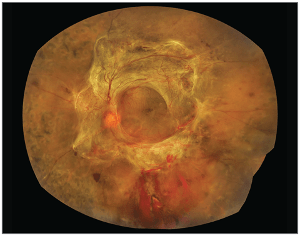

- These new blood vessels can form fibrous scar tissue.

- Scar tissue can pull on the retina and cause detachment of the retina called: tractional retinal detachment.

Tractional Retinal Detachment

- Vitrectomy

- In advanced PDR, where there is vitreous haemorrhage (bleeding) or tractional retinal detachment you may benefit from a vitrectomy.

- This is an operation involving the removal of the vitreous gel and blood and release of fibrous bands causing traction and pulling on the retina.